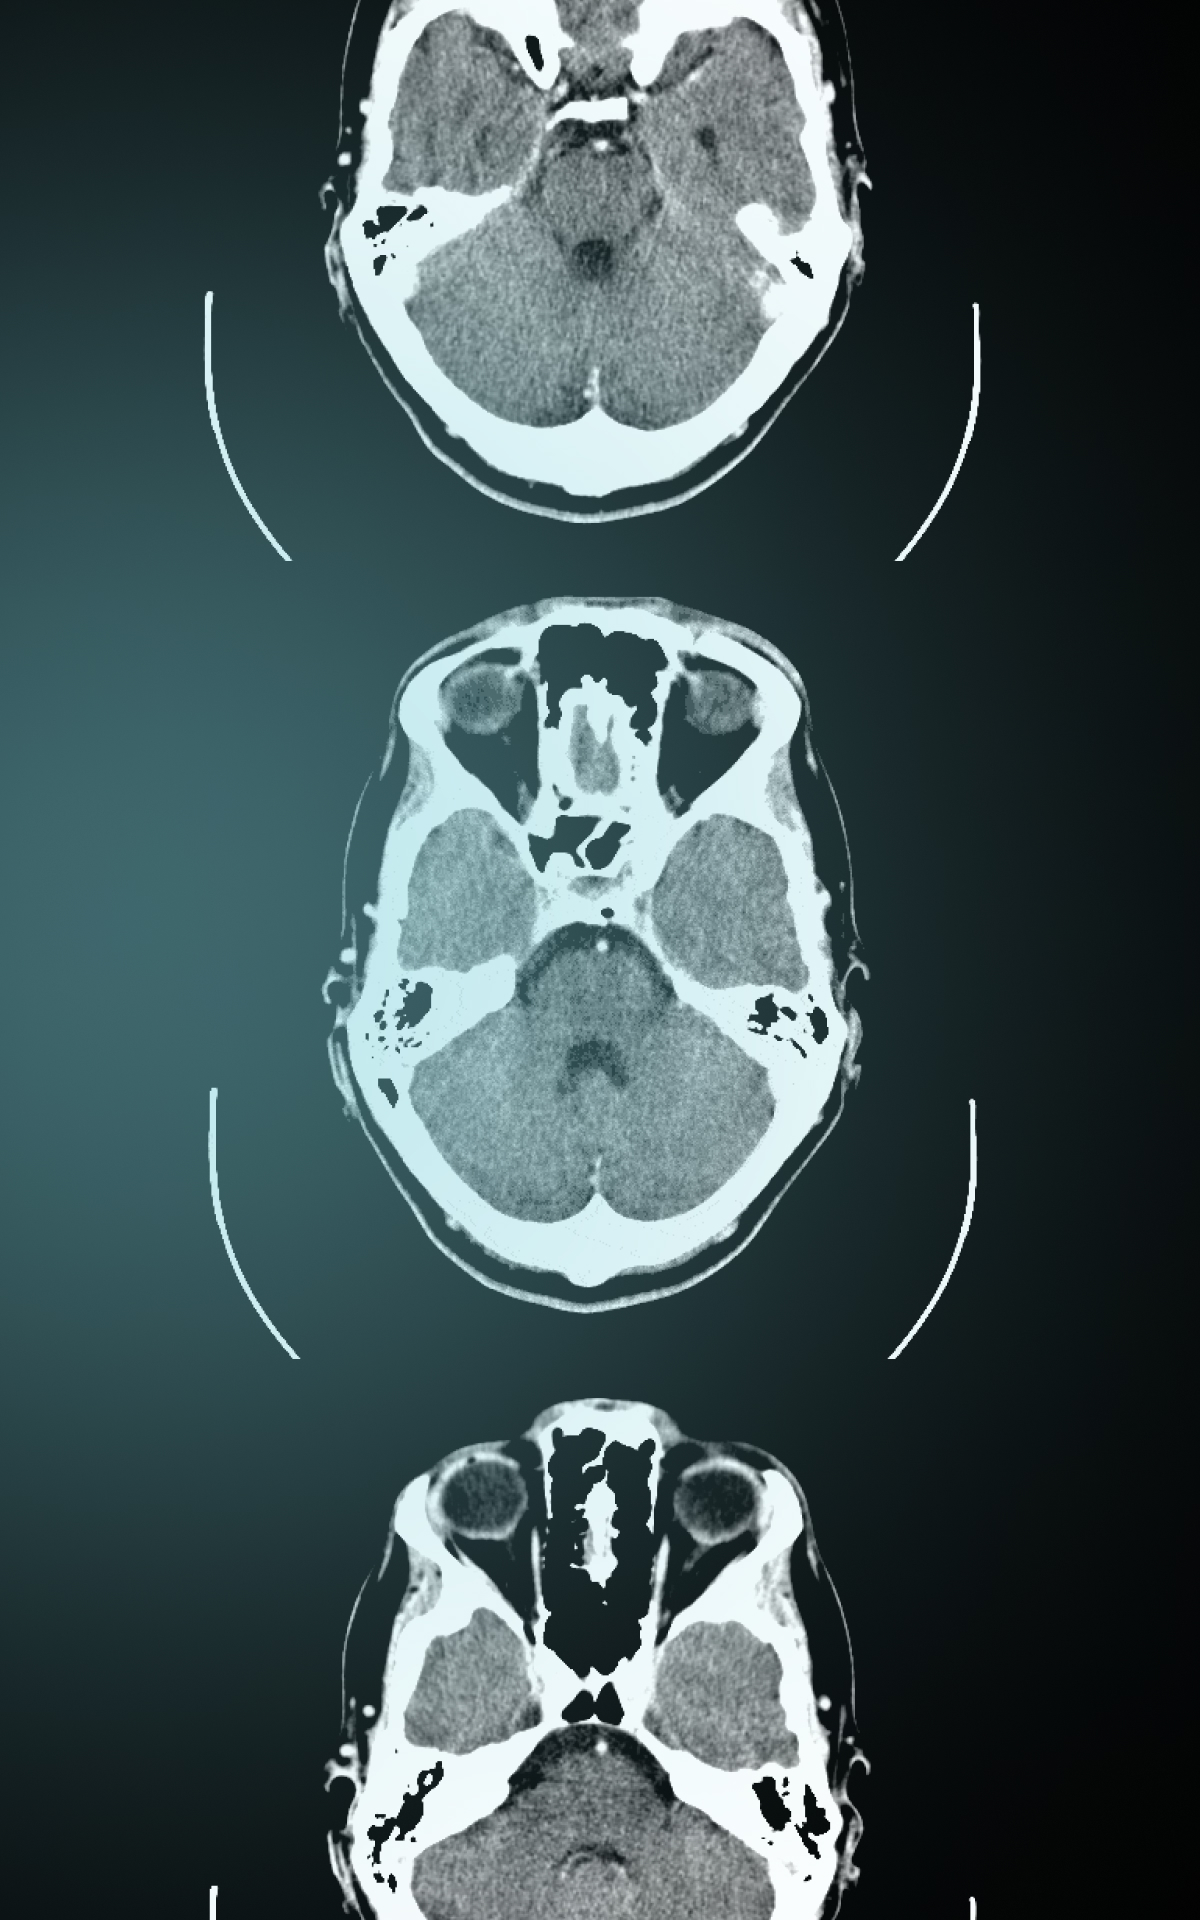

Marc Trabsky and Averyl Gaylor have co-authored a journal article for Social & Legal Studies that examines how radiological images became accepted by courts as visual evidence of death in the 20th century. Initially conceived as a speciality of photography, X-rays confounded courts, eliciting a range of judicial responses, from outright refusal to consider the images as any kind of evidence, to mocking them as cheap parlour tricks for an unwitting public, to recognising them as more reliable than the testimony of the expert witness. The article contends that courts moved towards recognising X-rays as proof of death only by both affirming forensic radiology's promise of ‘mechanical objectivity’ while acknowledging its reliance on the fallibility of ‘human subjectivity’. It suggests that this history has broader implications in socio-legal studies for comprehending how the invention of novel optical techniques continues to problematise legal epistemologies of death in the 21st century.

Post-mortem computed tomography (PMCT) has changed the experiences of bereaved people in coronial investigations. PMCT was developed by the Virtopsy® team initially at the University of Bern, but later at the University of Zurich, in the 1990s. It has been implemented in parts of Australia, Canada, Europe, Japan, UK, and USA since the early 2000s. When the technology is used as a triage tool to decide whether a medical cause of death can be found through CT scanning and an external examination of the body, it can decrease the rate of invasive autopsies in the coronial jurisdiction. For example, when the Victorian Institute of Forensic Medicine, located in Melbourne, Australia, introduced PMCT in 2005, the autopsy rate decreased by approximately 50%, and the rate of objections to autopsies by the next of kin also diminished.

Speaking before forensic scientists, Marc discussed the scope of his project on Virtual Autopsies and explained that post-mortem computed tomography has an important role in enabling coroners to meet the statutory objectives of coronial law, make recommendations for reducing the occurrence of preventable deaths, and carry out the administration of coronial justice.

Marc argued that virtual autopsies are inherently auto-optos, or to put this differently, they create the allure that judicial observers can see the interiority of the corpse with their own eyes. On the one hand, the post-mortem computed tomography appears to be more ‘objective’ than analogue technologies in determining the cause of a death. Yet on the other hand, like the images themselves which compose a body from multiple slices of data, ‘objectivity’ only takes shape through the mediation of mechanical instruments, computational techniques, and the medico-legal expert.